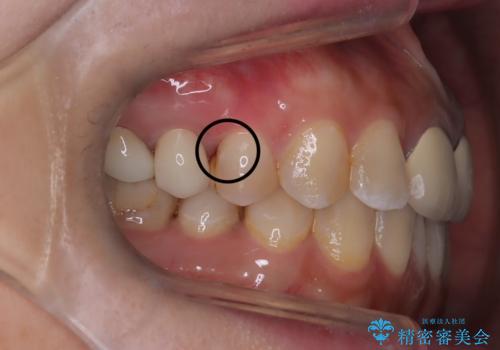

「右上4番目と5番目の間にフロスを通すといつも出血し、たまに臭いもする」という主訴で来院されました。

右上4番に歯冠色インレーが入っており、遠心側室エリアのマージン不適を認め、そこに汚れが溜まりやすい状態となっていました。